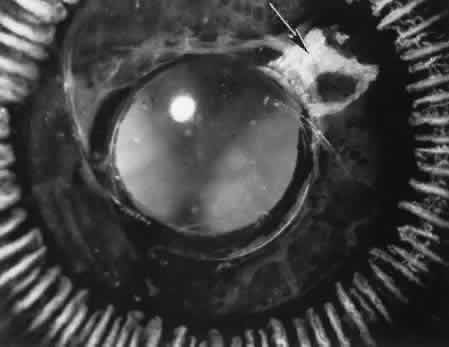

Epithelial downgrowth (ingrowth) (Fig. 44) is one of the most serious causes of pseudophakic glaucoma, in which surface epithelium (probably from the conjunctiva) grows into the anterior chamber. This condition is more likely to occur with fornix-based conjunctival flaps than with limbus-based flaps and in eyes with problems in wound closure, such as vitreous loss, wound incarceration of tissue, delayed reformation of the anterior chamber, or frank rupture of the limbal incision, and when instruments such as iridectomy forceps are contaminated with surface epithelium before they are introduced into the eye. Epithelial downgrowth causes an anterior chamber angle closure by means of peripheral anterior synechiae or lines an open anterior chamber angle and obstructs aqueous outflow mechanically. Histologically, the epithelium is seen to grow most luxuriously and in multiple layers on the iris where there is a good blood supply, but it tends to grow sparsely and in a single layer on the posterior surface of the avascular cornea. The epithelium may extend behind the iris, over the ciliary body, and even far into the interior of the eye.

Fig. 44. A case of epithelial downgrowth. A. The clinical findings are subtle and consist of a translucentmembrane on the posterior corneal surface, often contiguous with an ocular wound, characterized by a well-defined, linear leading edge. In this case, the leading edge is just above the corneal light reflex. B. In contrast, in this case, the leading edge is just below the corneal light reflex. The surgical procedure in both cases appears to have been complicated because of the presence of sector iridectomies. C. In this case, surface stratified squamous epithelium lines the posterior cornea (including the posterior aspect of the clear corneal wound) and extends over delicate trabecular tissue onto the anterior surface of the iris. The epithelium will adapt the tissue over which it grows to produce an adhesive surface appropriate to its attachment requirements. This adaptive process that is an advantage for the epithelium will permanently destroy the function of the trabecular meshwork over which the surface epithelium extends. D. The actual site of the fistula allowing the epithelium to gain access to the internal surfaces of the eye is rarely found on histologic sections. Higher magnification of the area of the wound, however, does show the presence of foreign material in the incision. Polarized material (inset) consistent with degenerating silk suture is present. Invasion of the epithelium along a suture tract is one possible route of entrance. (Hematoxylin-eosin stain with and without polarization; A, × 21; B, × 101)